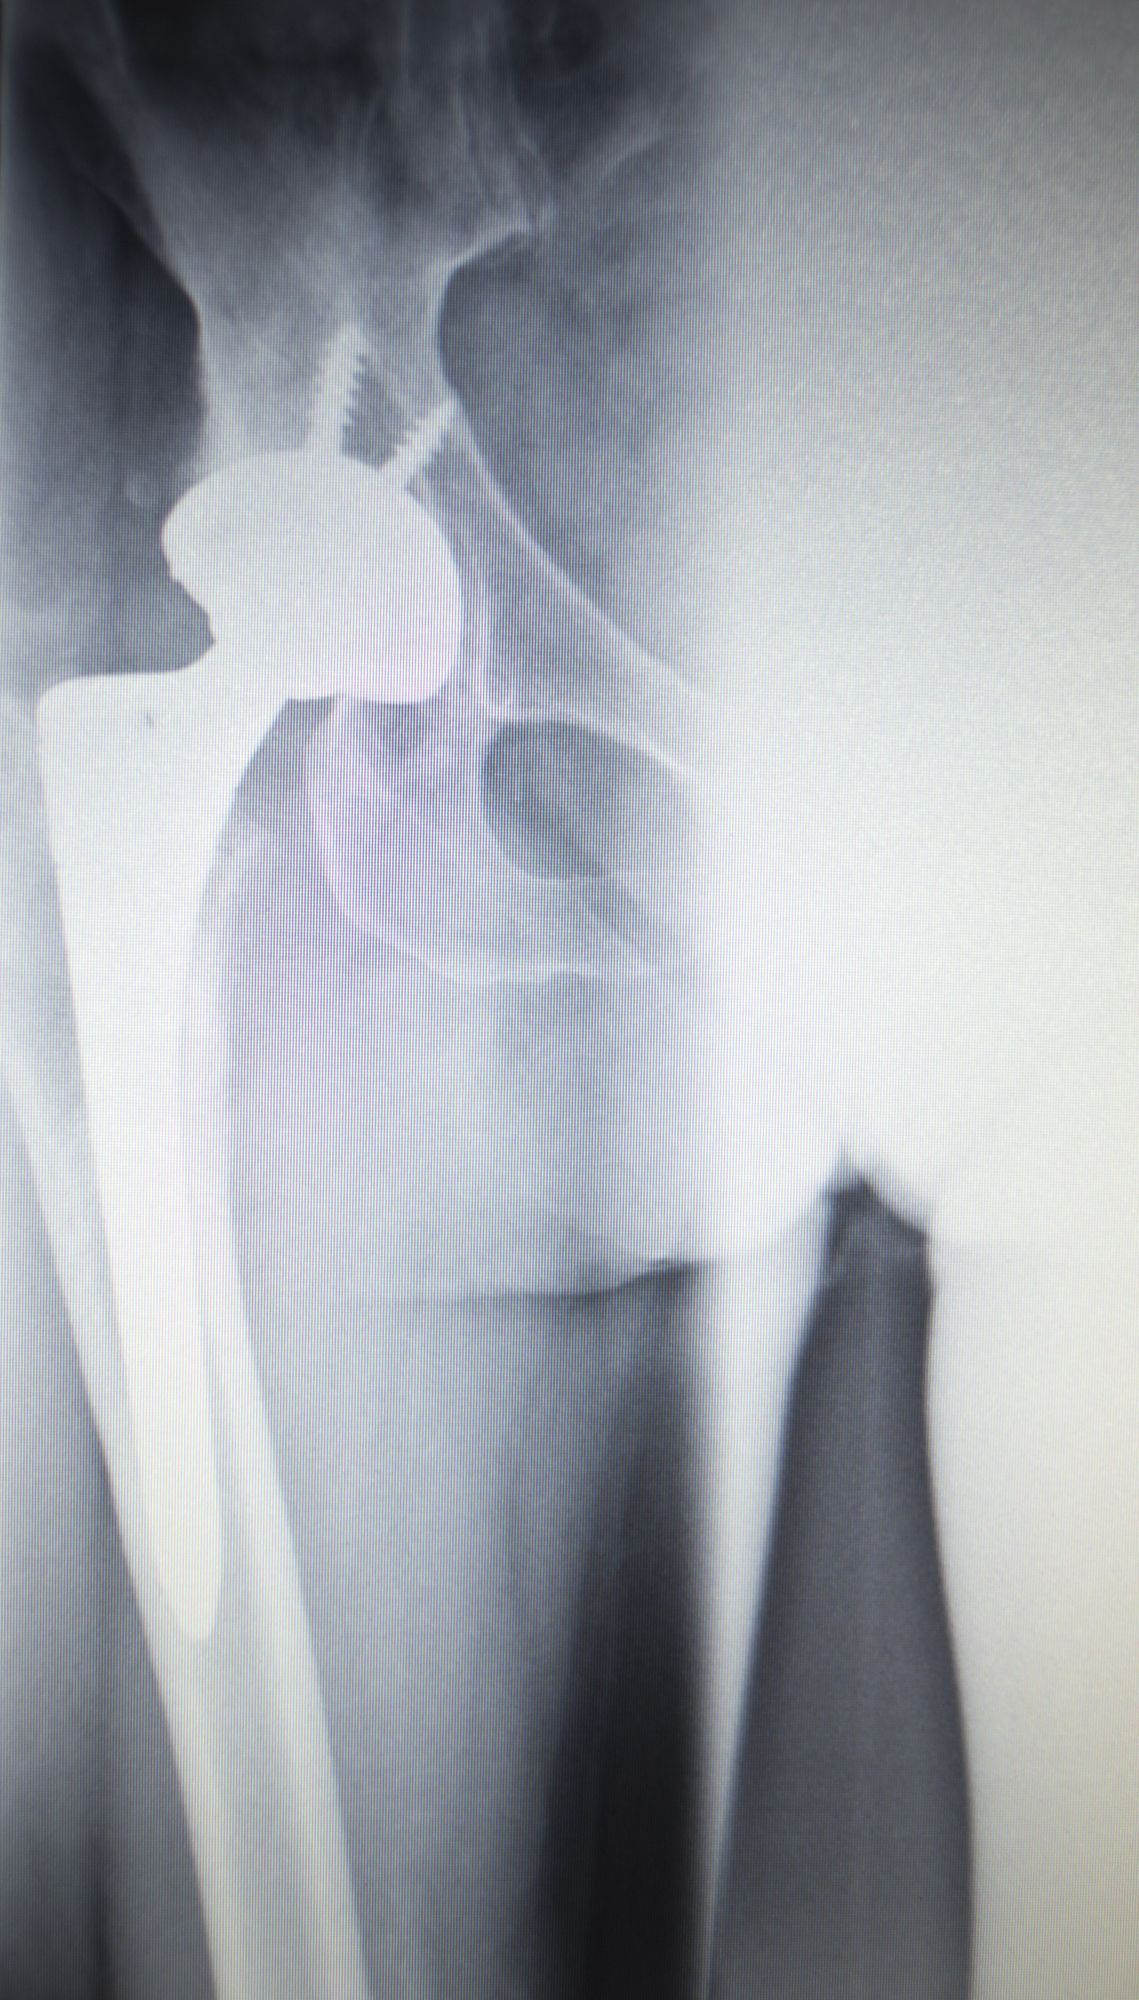

The DePuy ASR hip replacement system is a metal-on-metal hip system. What this means is that both parts of the ball-in-socket hip implant are metal.

In a metal-on-metal hip replacement, a metal cup called an acetabular cup is placed within the acetabulum on the pelvis. A metal ball replaces the femoral head and is connected to the femur by a metal stem.